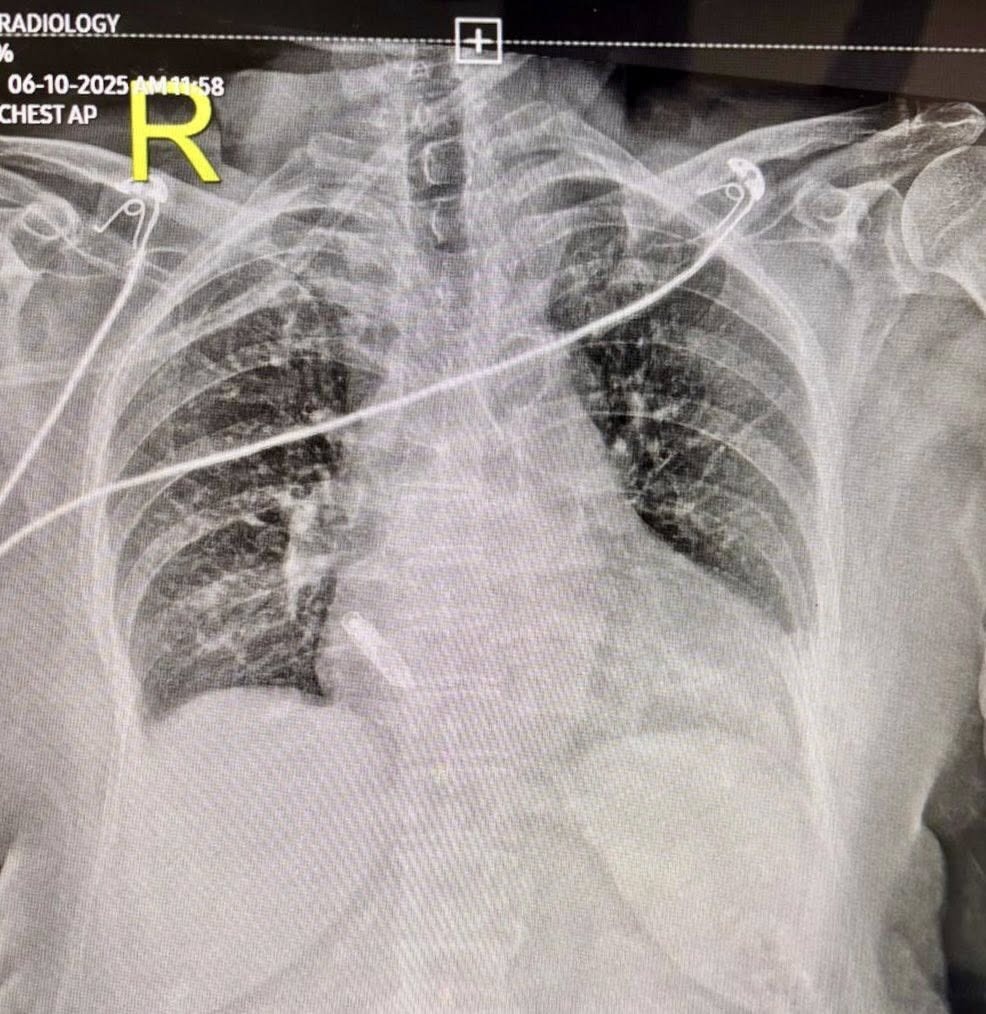

New Delhi: A 66-year-old woman has become the first patient in India to receive a leadless atrial pacemaker, following a minimally invasive procedure performed at Indraprastha Apollo Hospital in New Delhi.

Offering an alternative, Dr Vanita Arora, Clinical Lead for Cardiac Electrophysiology at Indraprastha Apollo Hospital, proposed the use of an Atrial Aveir Leadless Pacemaker—a capsule-sized, wireless device that can be implanted transcatheter into the right upper chamber of the heart, without the need for open surgery.

Successfully performed India’s first Atrial Aveir Leadless Pacemaker implant in a 66-year-old patient.